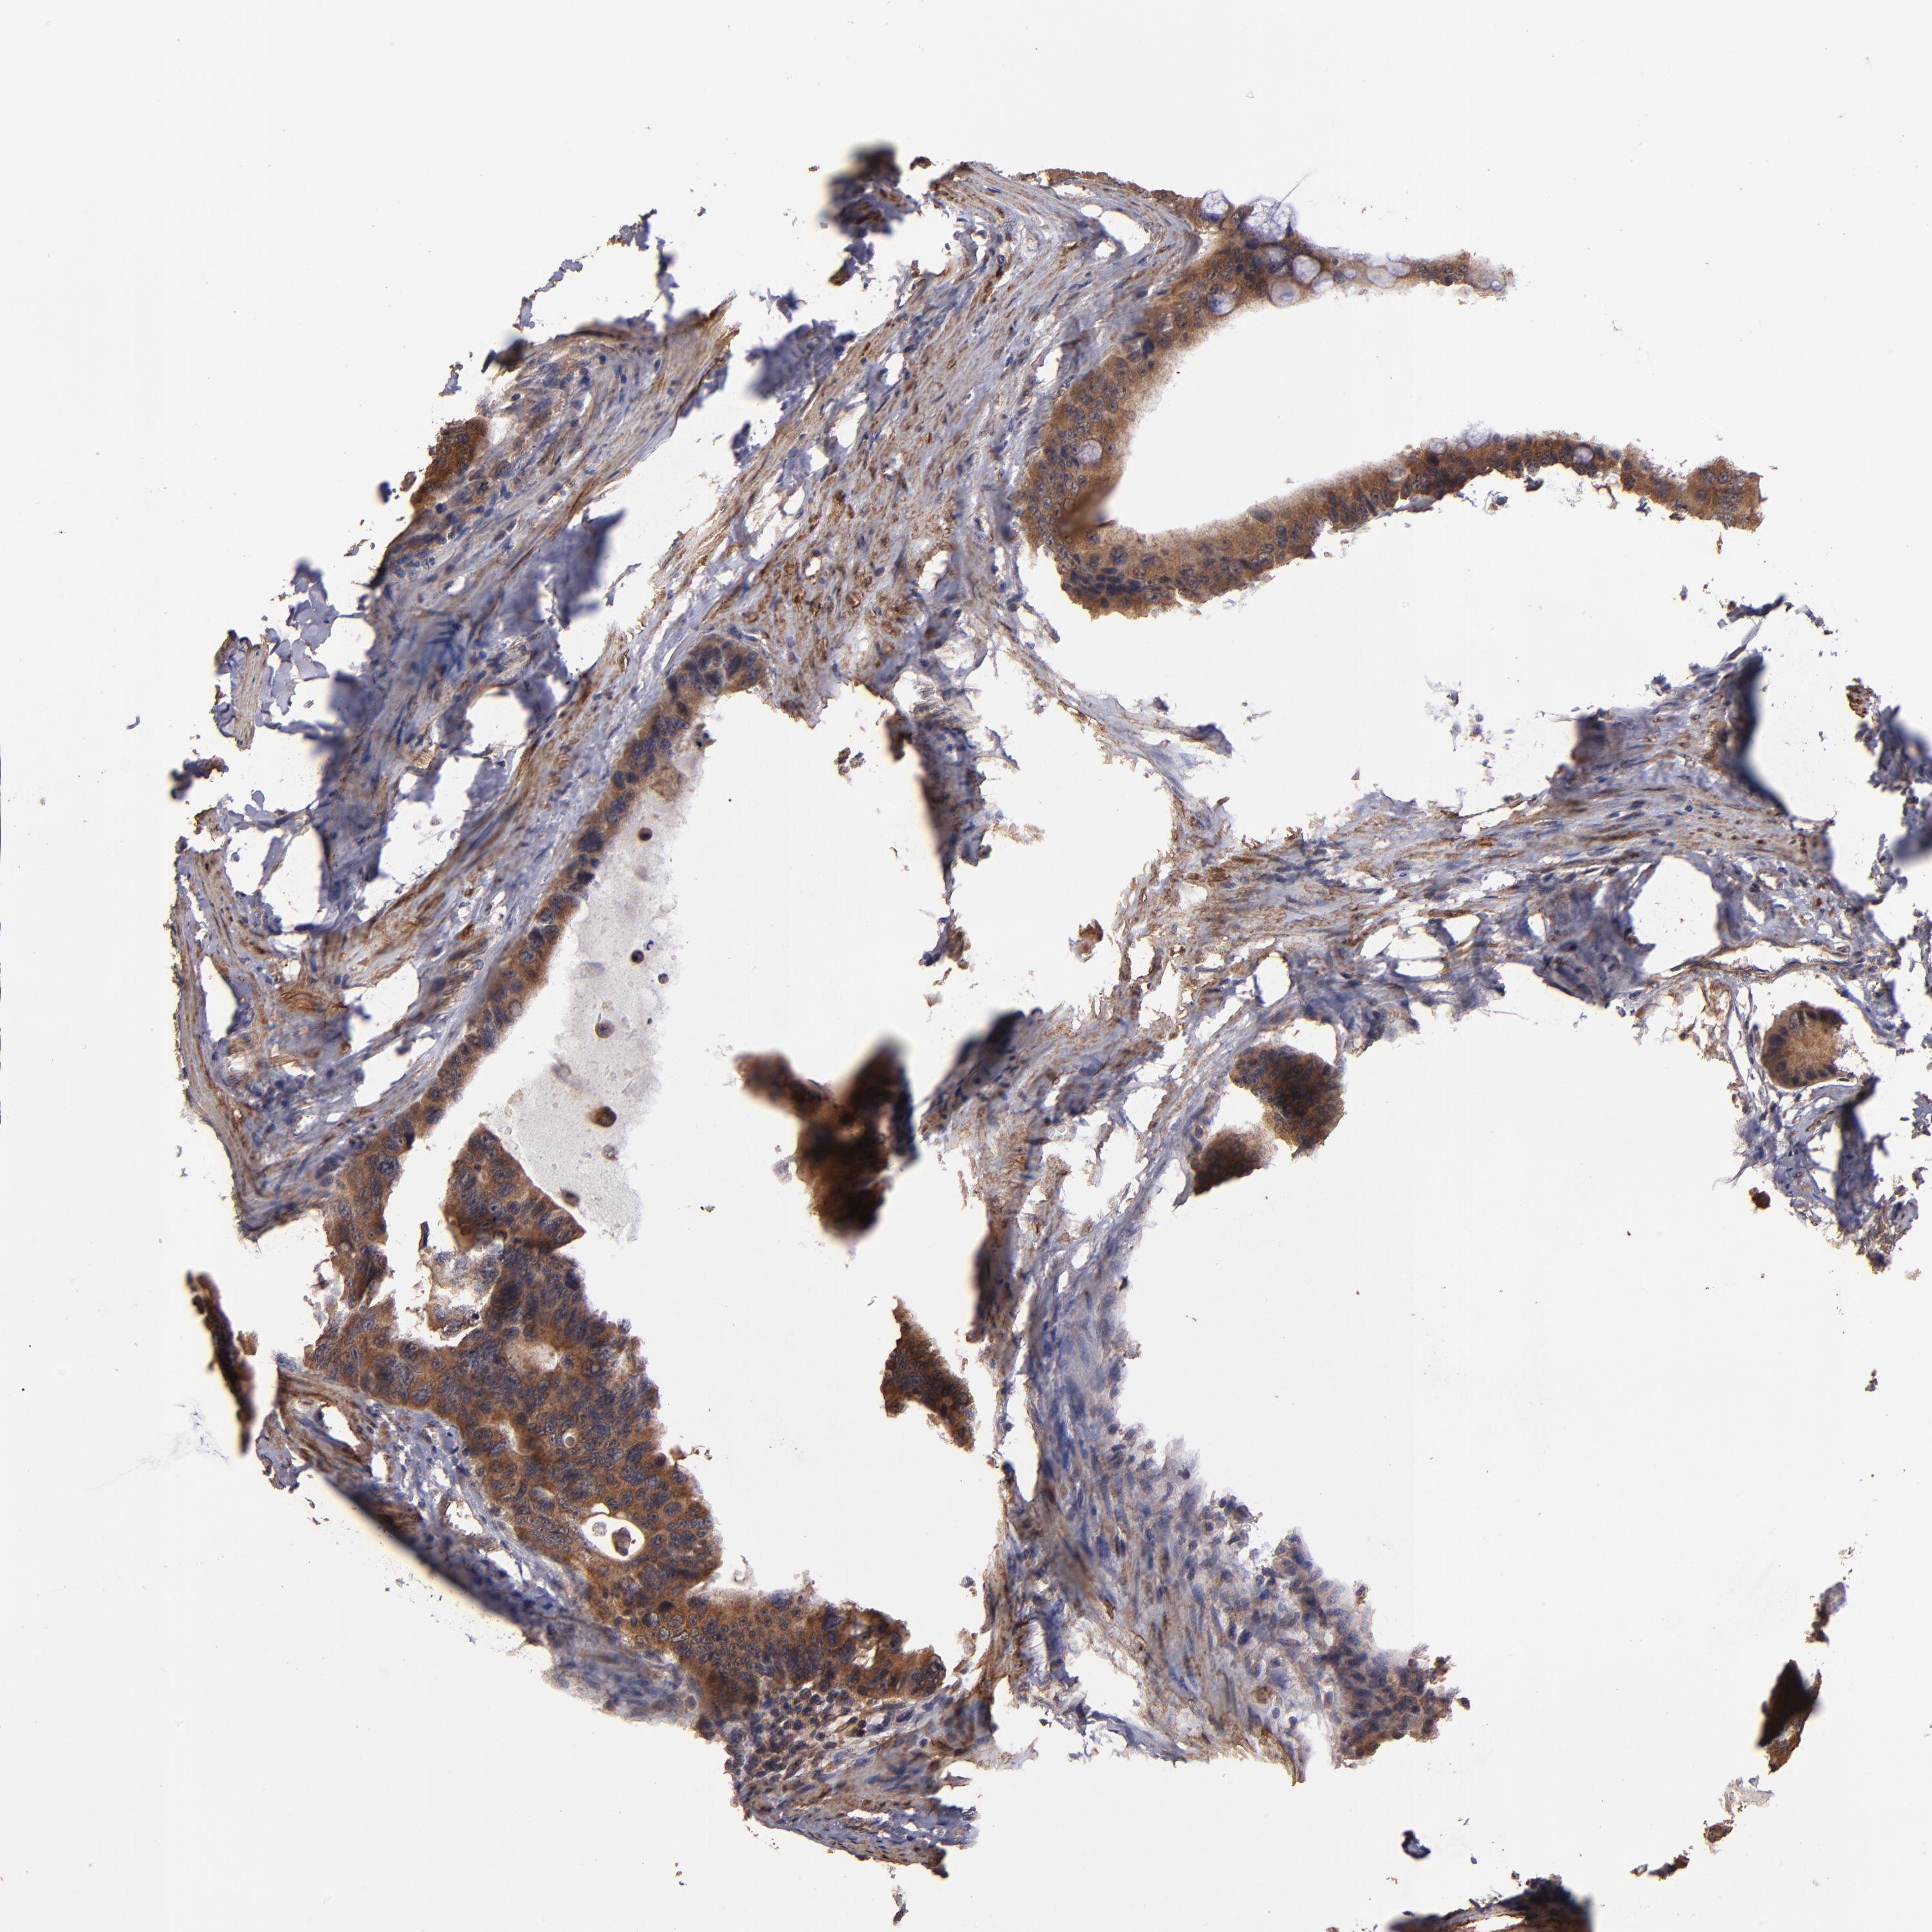

CANCER COLORECTAL CANCER Show tissue menu

Colorectal cancer

Human cancer

Colon adenocarcinoma